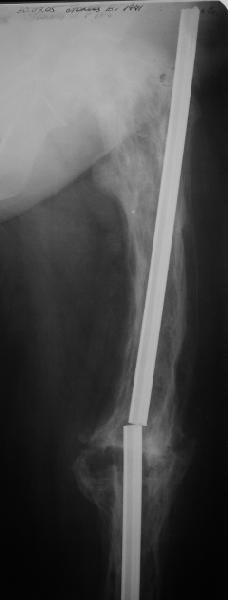

Re: перелом бедра на фоне болезни Педжета

Еще один пример. Пациентка с юга России, прислала рентгенограммы через год. На сегодня прошло 2 г. 8 мес. после операции. Несмотря на не очень убедительный процесс сращения, пациентка ходит. Учитывая остеопороз при Педжете, решили, что динамизировать вообще не нужно.